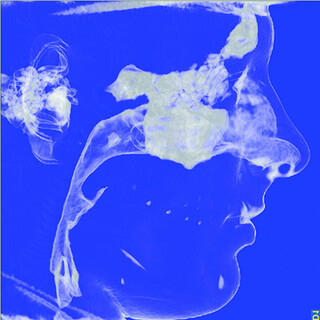

- Digitale Vermessung der oberen Luftwege

Bei im Schlaf erschlafftem Zungengrund kann im Krankheitsfall nicht mehr genügend Luft den Rachenraum durchströmen, was oft auch zum Schnarchen führt. Der Körper wird nicht ausreichend mit Sauerstoff versorgt. Typischerweise klagen betroffene Patienten über Tagesmüdigkeit und Leistungsminderung. Unbehandelt führt das OSAS oft zu chronischen Erkrankungen wie Bluthochdruck und Herzerkrankungen.

Ursächlich für ein OSAS kann z.B. auch ein zurückliegender Unterkiefer sein, welcher anatomisch den Zungengrund nach hinten drängt.

Mittels Zahnschiene (Protrusionsschiene) besteht die Möglichkeit, einen positiven Effekt der Unterkiefervorverlagerung zu testen und ggf. das Ausmaß der notwendigen Verlagerung festzustellen.

Durch eine Umstellungsosteotomie mit Kiefervorverlagerung (oft Ober- und Unterkiefer gemeinsam) kann das Krankheitsbild dann ursächlich behandelt werden.